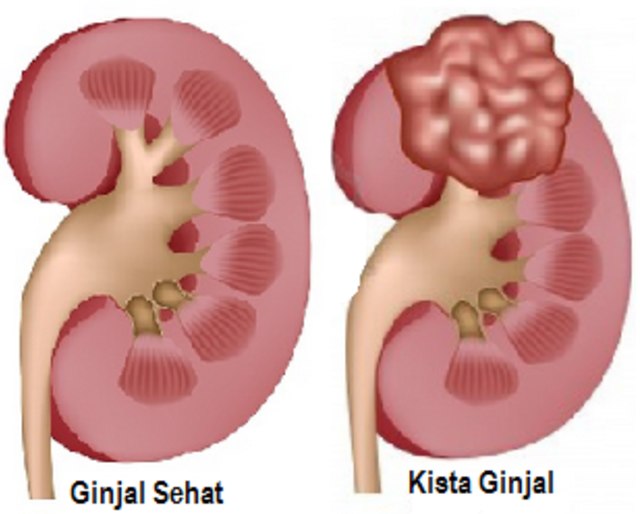

Cara Mengobati Kista Ginjal Secara Alami - kumparan.com

Cara Mengobati Kista Ginjal Secara Alami - kumparan.com

Kista Ginjal - Gejala, Cara Menangani, dan Pengobatannya | HonestDocs

Kista Ginjal - Gejala, Cara Menangani, dan Pengobatannya | HonestDocs